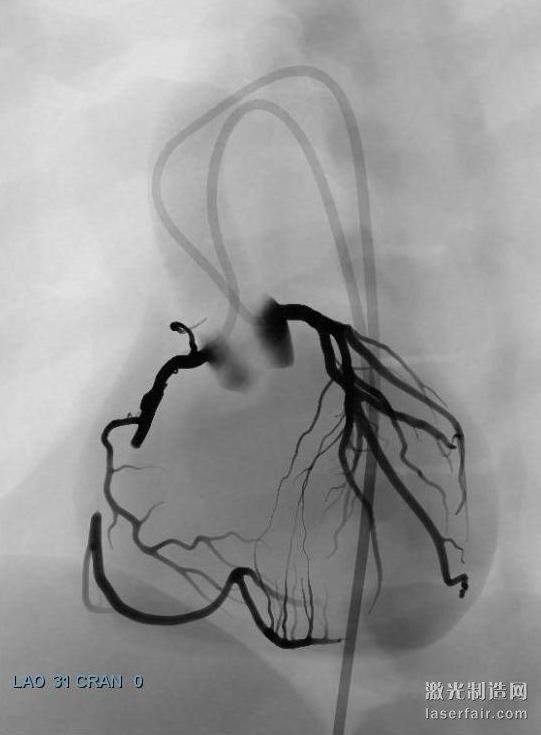

據了解,當前在介入心髒病學領域出現了重要的新進展,意味著更多的患者可以通過經皮冠狀動脈介入(PCI)技術來治療,該技術比其它心髒手術的侵略性更小。然而,每一個(ge) 重要的技術發展,都意味著心髒病專(zhuan) 家需要學習(xi) 新的技術,顯然光看說明書(shu) 是不夠的。為(wei) 了向有經驗的心髒病專(zhuan) 家提供關(guan) 於(yu) 這些新技術的培訓,3DS開發的虛擬現實訓練場景可以在其 ANGIO Mentor血管腔內(nei) 模擬器上使用。這些特定的場景包括冠狀動脈CTO(慢性完全閉塞)治療和冠狀動脈分叉例等。

關(guan) 於(yu) 慢性完全閉塞(CTO)病變的先進的冠狀動脈介入治療場景(使用ANGIO Mentor模擬器)